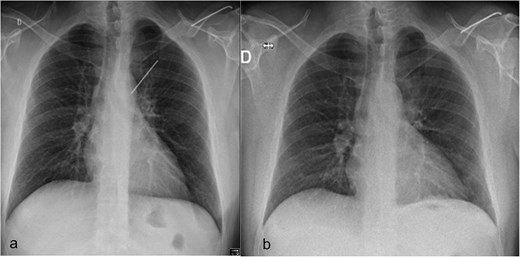

Surgical removal of the K-wire was indicated because of the symptoms and the risk of further migration with harm to elements of the bronchial or vascular system. A preoperative chest X-ray confirmed that the position of the pin was unchanged since the CT scan (Fig. 2).

(a) Preoperative chest radiograph with 6.2 cm long K-wire in the left hemithorax. The lateral half of the pin (6.4 cm), located in the distal part of the left clavicle. (b) Postoperative chest radiograph with complete lung expansion after chest tube removal.